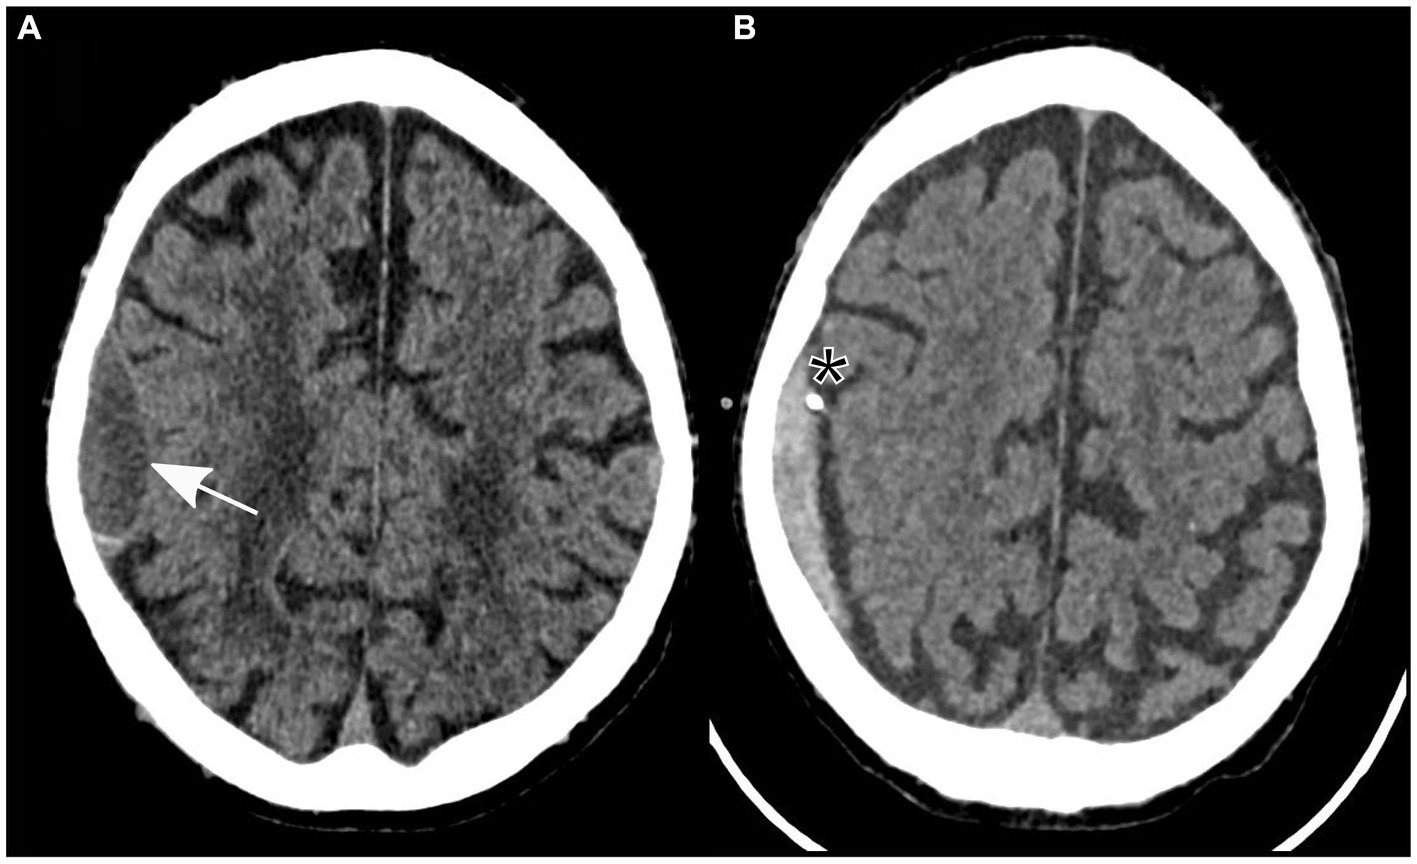

Further examination was necessary after the patient experienced sudden left-sided hemiparesis that fluctuated in severity following elimination of a pulmonary embolism. There was no sign of a traumatic event at any point during clinical presentation. A non-contrast cranial CT scan was conducted, which indicated a low-volume subdural hematoma localized to the right parietal hemisphere (Figure 1A). Importantly, no evidence of other intracranial pathologies was detected in the initial CT scan. In addition, the patient reported no relevant headaches, nausea, or vomiting.

Figure 1

Non-contrast axial computed tomography showing a subdural hematoma in the parietal lobe (identified by an arrow) prior to (A) and following insertion of a subdural drain (asterisk) through a twist-drill craniostomy (B).

Owing to the severity of the patient’s neurological findings, he was transferred to our tertiary referral hospital for specialized care. A twist-drill craniostomy was performed, and a subdural drain was inserted parietally in the right hemisphere due to the size of the subdural hematoma and its neurological symptoms. In preparation for the surgical procedure, 3,500 international units of prothrombin complex concentrate were administered to safely reverse the effects of anticoagulation therapy.

After the patient underwent successful surgery, he was transferred to the standard ward for postoperative monitoring. Nevertheless, the following morning, the patient displayed new neurological symptoms, such as dysarthria and exacerbated left-sided hemiparesis. A subsequent cranial CT scan verified the correct positioning of the subdural drain and revealed a decrease in the size of the subdural hematoma (Figure 1B). Sudden onset of dysarthria and worsening hemiparesis on the left side during the postoperative phase necessitated further imaging. Follow-up cranial CT revealed a decrease in the size of the subdural hematoma; however, this could not explain the aggravated neurological symptoms. An MRI scan of the brain revealed the coexistence of an ischemic stroke in the hyperacute phase of the right corona radiata in the supply area of the right anterior choroidal artery. It exhibited increased brightness on diffusion-weighted imaging (DWI) and reduced apparent diffusion coefficient (ADC) values (Figure 2). Further neurological assessment revealed moderate stenosis of the left middle cerebral artery in the distal M1 segment. A pivotal clinical challenge that has emerged is the lack of clear guidelines on the timing of antithrombotic restart following the occurrence of SDH. This challenge was further compounded by the high risk of very early stroke (within 24 h) in our patient, who presented with recurrent TIAs suggestive of CWS. Given this high risk, the immediate initiation of secondary prevention is a critical consideration. However, considering the recent surgery and the absence of large intracranial artery occlusion, no antithrombotic treatment was initiated.